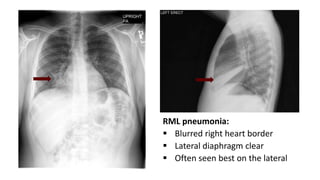

57 year old with cough

and shortness of

breath.

The CXR demonstrates:

a. Pulmonary edema

b. RLL pneumonia

c. RML pneumonia

d. Pulmonary embolus

e. Lung cancer

RML pneumonia:

ď‚§ Blurred right heart border

ď‚§ Lateral diaphragm clear

ď‚§ Often seen best on the lateral